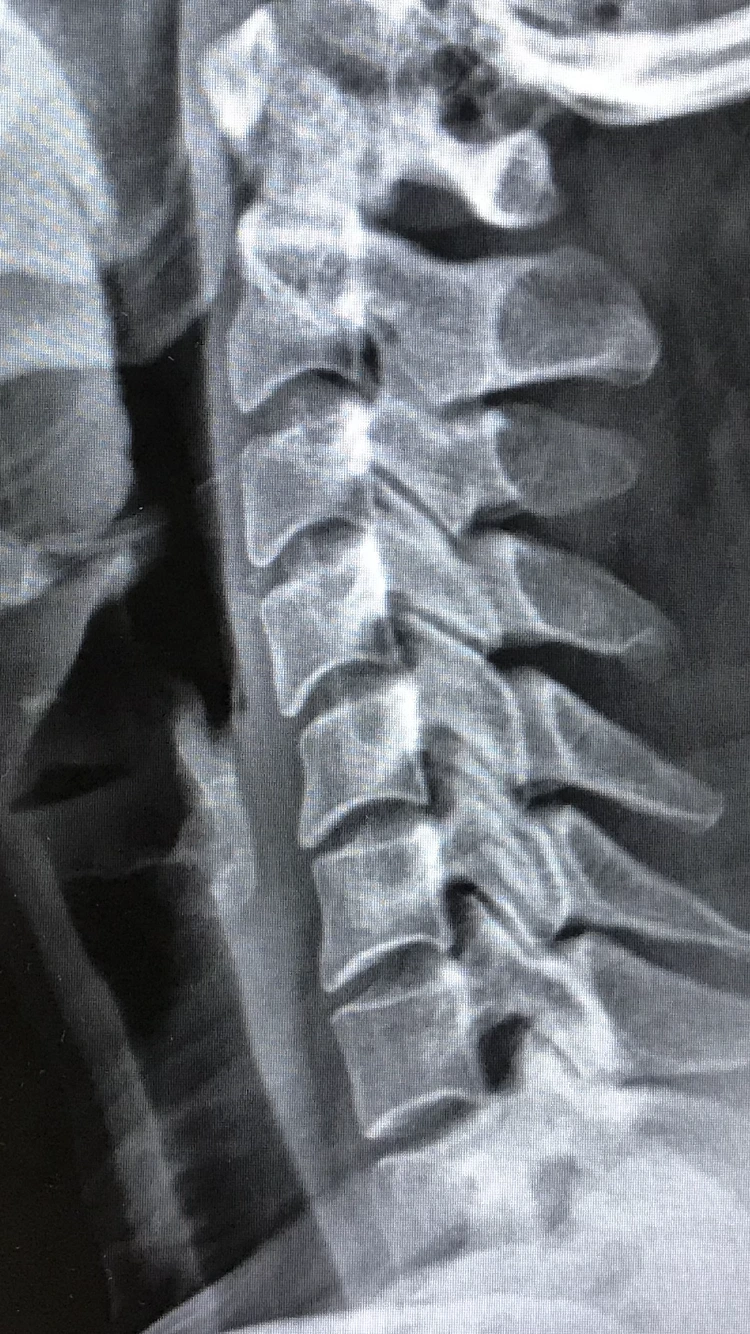

요즘 일자목 증상을 완화하려고 마사지를 받고 있다. 바디워크 진행자인 아일린 언니 왈. ‘그냥 되는대로 살아’

척추 기립근이 죄다 ‘나 바르게 살고 있소 ‘ 하듯 긴장되어 있다고. ㅋㅋㅋ 나만의 스트레스는 대부분 바르고자 혹은 바로 잡고자 하는 욕망에서 비롯된다. 할 일이 없거나 쉬는 것도 종종 스트레스일 때가 있다.